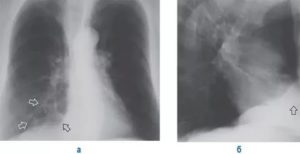

Для визуализации патологического процесса назначается рентгенологическое исследование органов грудной клетки, которое позволяет обнаружить изменения в легких. Обнаруживаются изменения с обеих сторон, преимущественно в нижних отделах легких.

Отмечаются усиление и деформация легочного рисунка, постепенно формируется картина так называемого «сотового легкого», которое характеризуется образованием кольцевых теней диаметром 3 – 7 мм со стенками толщиной до 3 мм, что в некоторой мере напоминает пчелиные соты.

Более детальную оценку структурного состояния легких дают компьютерная томография (КТ) и магнитно-резонансная томография (МРТ). В тяжелых случаях, когда вышеперечисленные методы исследования не позволяют выставить правильный диагноз, прибегают к помощи биопсии легкого, которая позволяет подтвердить наличие рубцовой ткани на микроскопическом уровне.